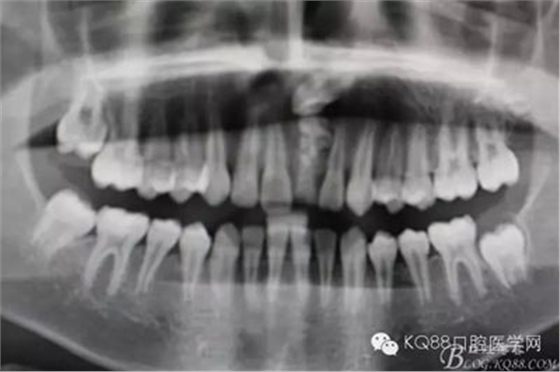

圖2.全景片影像檢查:牙冠接近鼻底,位置高,橫位阻生,正畸牽引有點困難,故同家長溝通,有牽引失敗的可能。同時暫時保留乳Ⅰ。不影響孩子的美觀及發(fā)音。